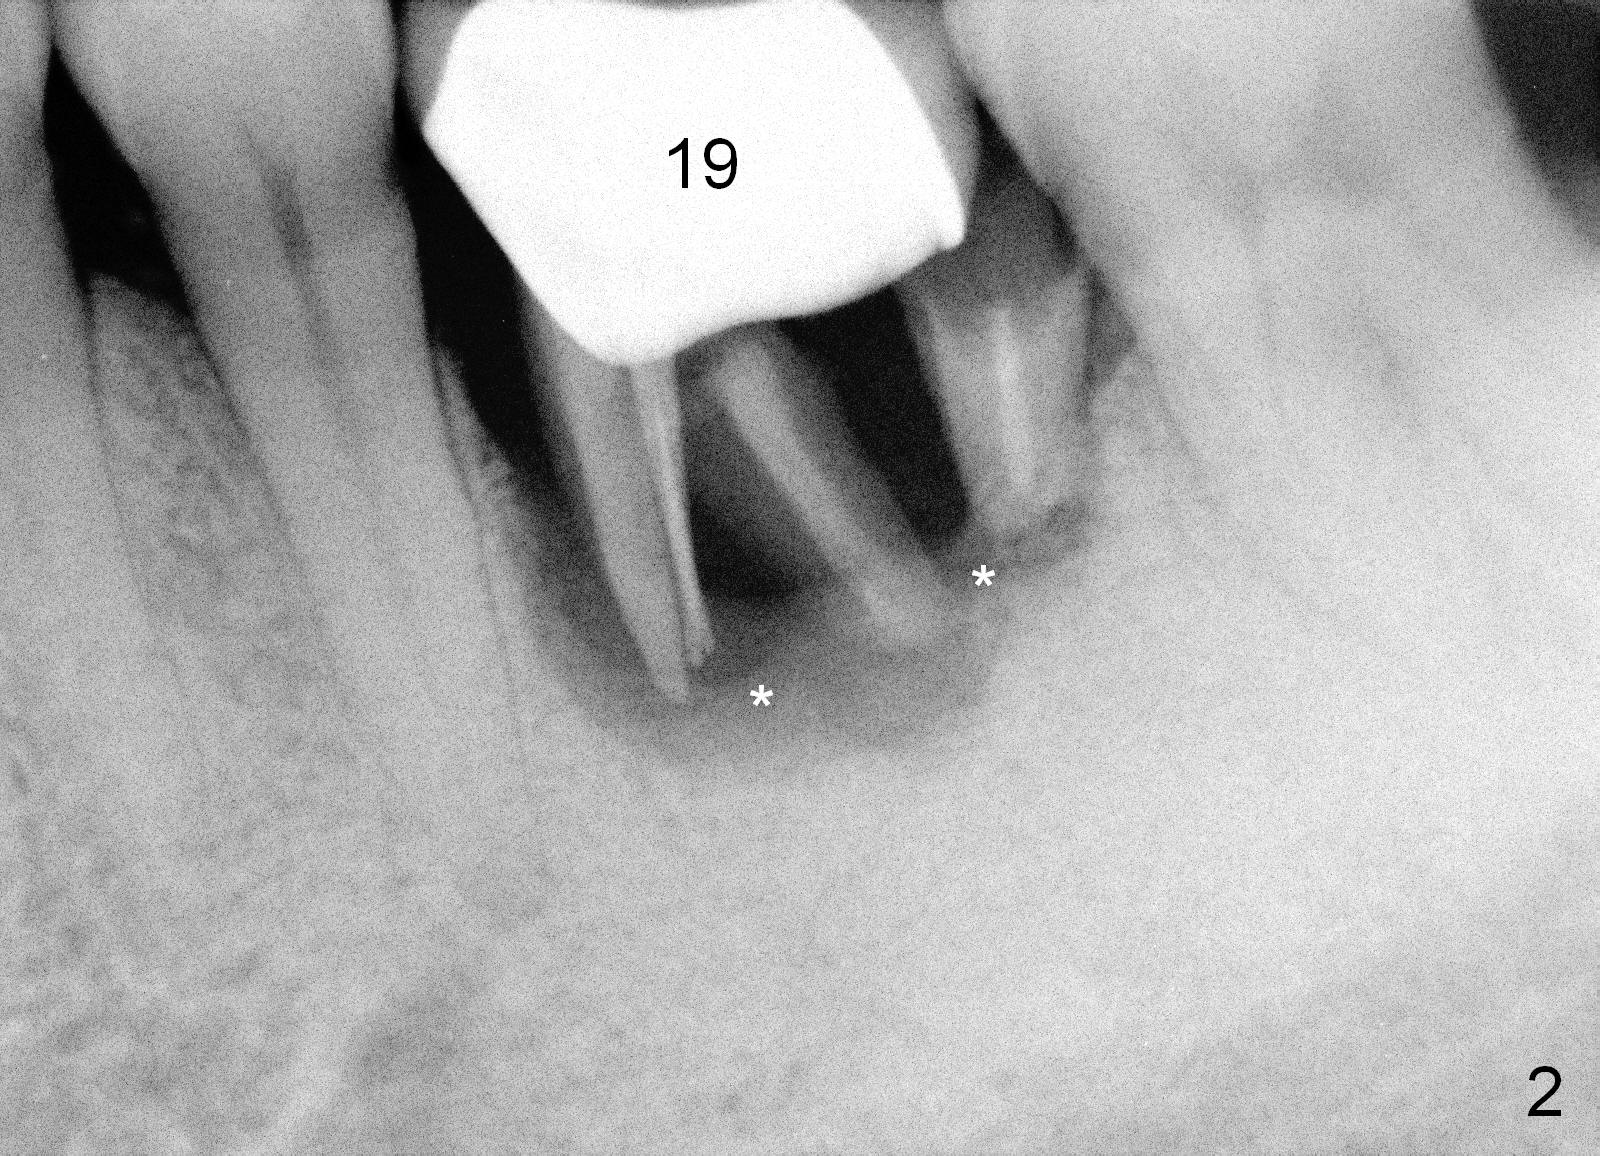

ridge wide, 19 crown buccal gingival erythema, edema and recession, PA taken. It

shows # 19 root fracture, severe bone loss (Fig.2 *)

A: 19 nonsalvageable, partial

edentulism